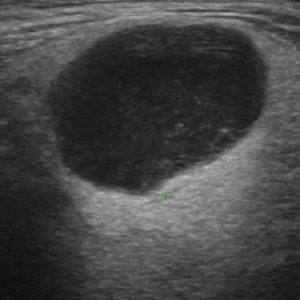

U tuyến nước bọt

Lượt xem: 138» 19-01-2021 -

U tuyến nước bọt

Lượt xem: 153» 19-01-2021 -

U tuyến nước bọt

Lượt xem: 131» 19-01-2021 -

U tuyến nước bọt

Lượt xem: 102» 19-01-2021 -

U tuyến nước bọt

Lượt xem: 146» 19-01-2021 -